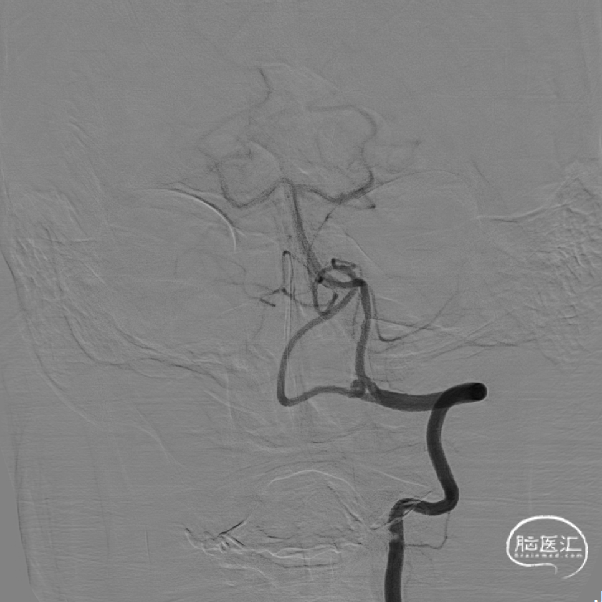

患者术前DSA:左椎动脉开口重度狭窄,左椎动脉颅内正侧位造影显示后循环血供正常。

支架植入后可看见椎动脉起始部狭窄病变处明显改善。

术前造影

术后4年7个月复查DSA造影示支架内再狭窄。

术后正侧位造影:

术后再8个月复查造影,支架形态良好,DSA随访,管腔通畅,未见再狭窄。

术后再8个月左侧椎动脉复查造影,血管通畅。